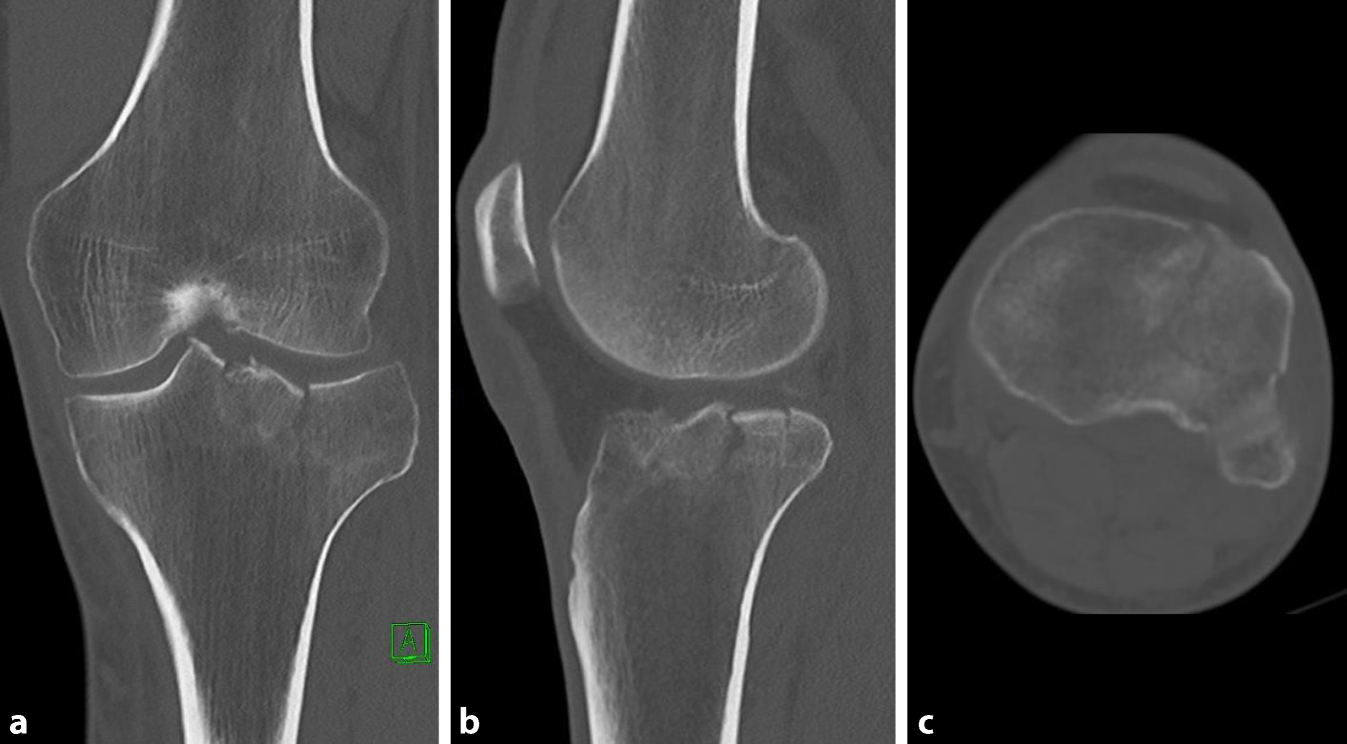

Abb. 2

Computertomographie der lateralen Tibiaplateaufraktur (AO [Arbeitsgemeinschaft Osteosynthese] 41B1.1). Mittels der Darstellung in drei Ebenen (a frontal, b sagittal und c axial) erkennt man neben dem anterolateralen Fragment eine weitere posteromedial verlaufende Frakturlinie, die im Röntgenbild (s. Abb. 1) nicht zu erkennen gewesen ist

Untersuchungen konnten zeigen, dass eine zusätzlich angefertigte CT-Aufnahme die Frakturklassifikation in 12–71 % der Fälle änderte, das operative Vorgehen wurde dabei bei 26–59 % der Patienten revidiert (Abb. 2; [4, 14, 16, 23, 28]). Die Inter- und Intraobserver-Reliabilität zeigten im Vergleich zur rein nativradiologischen Bildgebung bezogen auf die Schatzker- und AO (Arbeitsgemeinschaft Osteosynthese) -Klassifikation eine signifikante Verbesserung [2, 3]. Dabei ist das CT vor allem beim Nachweis von posteromedialen und -lateralen Frakturen sinnvoll, da diese häufig auf der nativradiologischen Aufnahme übersehen werden ([24]; Abb. 2).

Diese Ergebnisse sowie die flächendeckende Verfügbarkeit qualitativ hochwertiger Computertomographen haben die native CT-Bildgebung bei Tibiaplateaufrakturen als Goldstandard bei der Diagnostik und präoperativen Planung etabliert. Insbesondere bei der Diagnostik koronarer Frakturlinien, die bei komplexen Tibiaplateaufrakturen mit einer Inzidenz von 30–39 % auftreten, zeigt sich das CT im Gegensatz zum klassischen Röntgen führend, da diese konventionell radiologisch häufig nicht erkannt werden (Abb. 1 und 2; [2, 3, 21]).